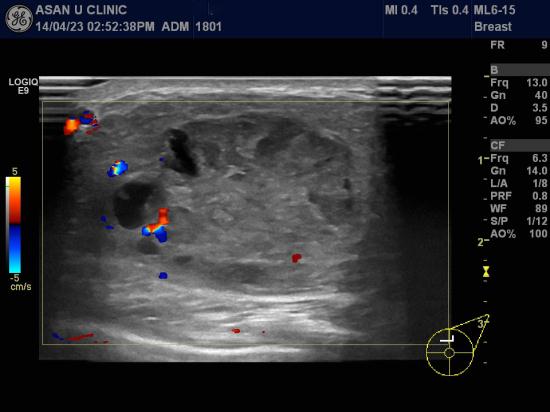

몇 달전부터 커진 유방의 몽울로 내원한 48세 여성입니다.

만져진다는 부위에, 3cm 이상의 혹과

3시방향으로도 3.68cm의 타원형의 혹이 있었습니다.

같은방향에 겨드랑이 림프절에도 4개이상의 비대된 소견이 있었습니다.